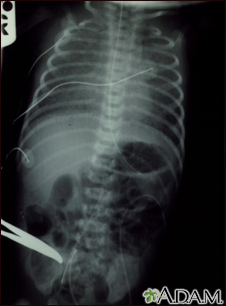

Totally anomalous pulmonary venous return - X-rayBackTotally anomalous pulmonary venous return - X-rayTotally anomalous pulmonary venous return (TAPVR) is a form of congenital heart disease. E-mail FormEmail ResultsName:Email address:Recipients Name:Recipients address:Message: